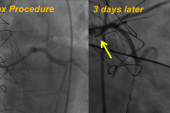

In May 2025, the team performed the VECTOR procedure successfully, anchoring the covered stent to both the LAD and aorta with drug-eluting stents. They then performed balloon-expandable TAVI using Sapien3 Ultra Resilia. Total procedure time was 8 hours and 40 minutes, and total fluoroscopy time was 226 minutes.

The stent graft was patent on CT the day after the procedure, and the patient remains well more than 6 months later. He is currently taking lifelong oral anticoagulation.